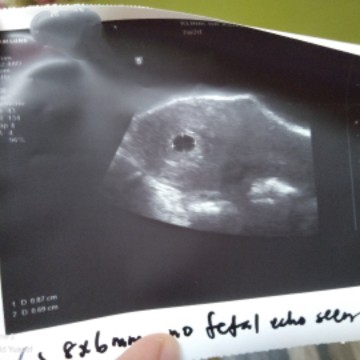

Saya baru scan Sabtu baru ni.doc cakap kecil lagi,susah nak ukur due date n tengok jantung baby.So doc suruh repeat scan lagi 2minggu.Semoga hasil scan nanti baik-baik saja.aamiin

sy pun kena repeat scan jgk .. msa 9weeks kantung ad , janin ad tp heartbeat xnmpk .. Btapa rsaunya sy , lagi cemas bila ad yg komen "sy 5-6 weeks dah ad kantung , ad janin , ad heartbeat" ... Smga sis tbah , sma2 kita berdoa agar Allah melindungan kandungan kita , Allah selamatkan zuriat yg sdah ada dlm rahim kita .. Aameen 🤲🏻

Sama saya sis ,saya scan baru ni pun just nmpak kantung , besar mcm sis laa scan dari bwah sebab kat perut Tak nampak dktor sruh dtg lagi 2 mnggu untuk tgk jantung plan moga2 ada aminnn

Rasanya ni awal sgt ni.. Mgkin baru 4 5week..tggu 8@9 w sis.. Bru senang nk ukur due dgn heartbeat